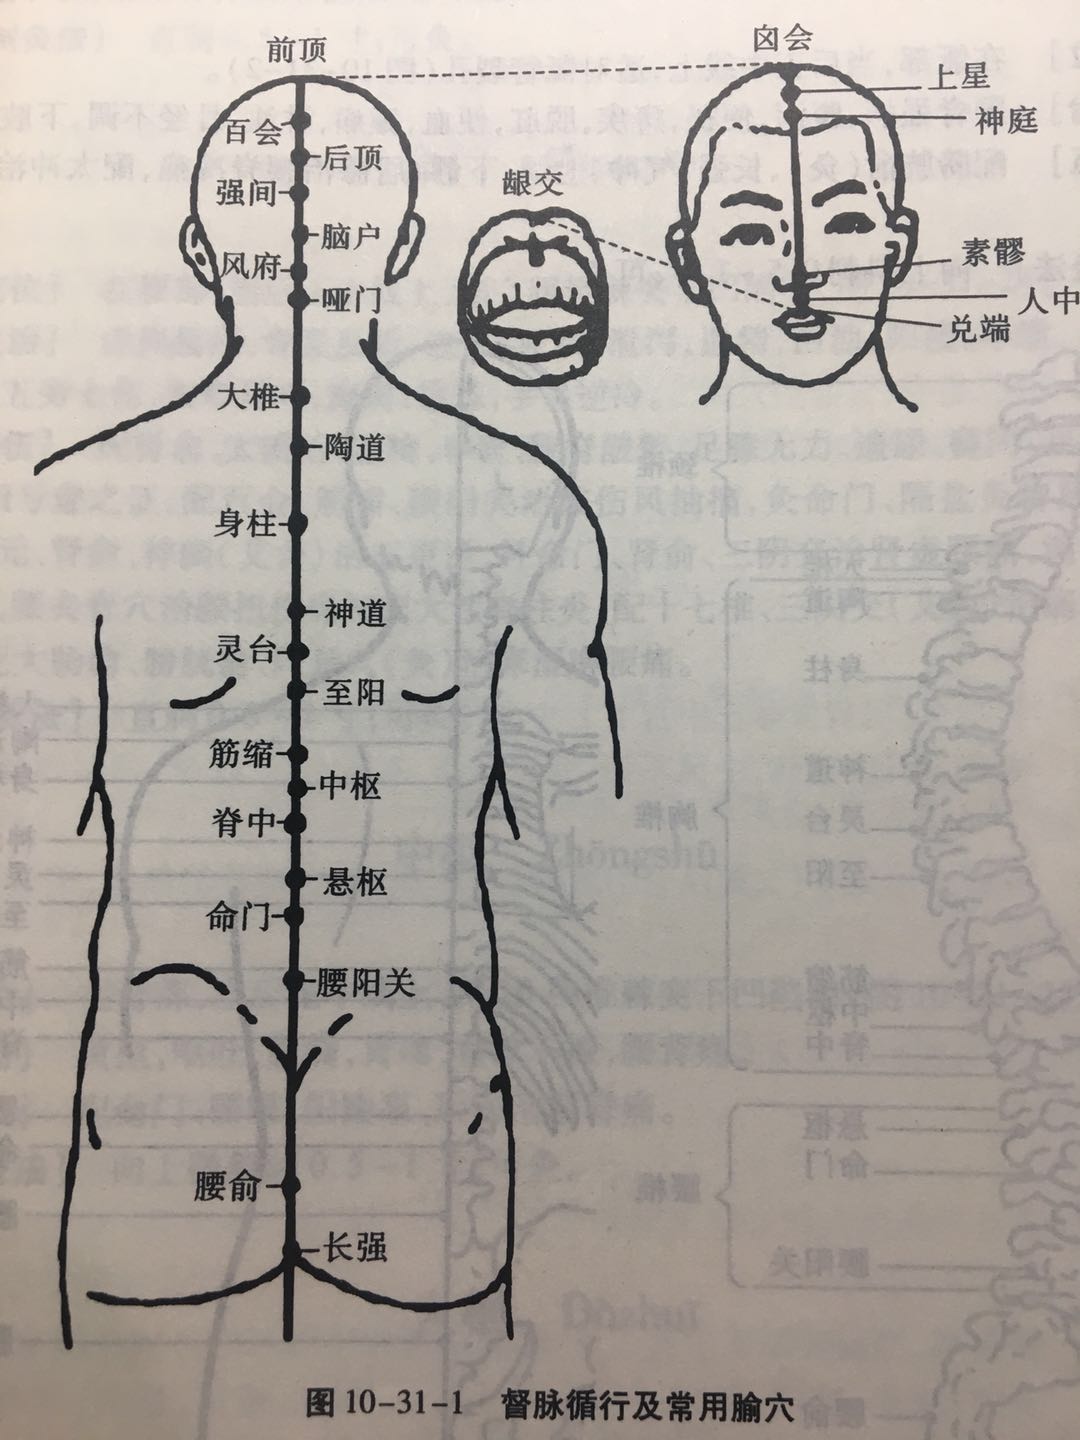

【(十三)督脉(图10-31-1)】

1、经脉循行 起于小腹内,下出于会阴部,向后行于脊柱的内部,上达项后风府,进入脑中,上行巅顶,沿前额下行鼻柱。

2、主要病候 脊柱强痛,角弓反张等证。

3、主治概要 神志疾病,热病,腰骶、背、头项、生殖疾患及循行所过部位相应内脏病证。

4、督脉歌诀 督脉行背之中行,二十八穴始长强。腰俞阳关入命门,悬枢脊中上中枢。筋缩至阳归灵台,神道身柱陶道周。大椎哑门连风府,脑户强间后顶排。百会前顶通囟会,上星神庭素髎对。水沟兑端在唇上,龈交上齿缝之内。

腰俞

【定位】 在骶部,当后正中线上,适对骶管裂孔(图 10-31-2)。

【主治】 腰脊强痛,腹泻,便秘,痔疾,脱肛,便血,癫痫,淋浊,月经不调,下肢痿痹。

【配伍】 配膀胱俞(灸)、长强、气冲、上髎、下髎、居髎治腰脊冷痛,配太冲治脊强反折、抽搐。

【刺灸法】 向上斜刺 0.5 ~ 1 寸;可灸。

腰阳关

【定位】 在腰部,当后正中线上,第 4 腰椎棘突下凹陷中(图 10-30-2)。

【主治】 腰骶疼痛,下肢痿痹,月经不调,赤白带下,遗精,阳痿,便血。

【配伍】 补腰阳关、肾俞、次髎,泻委中治腰脊痛、四肢厥冷、小便频数;配腰夹脊、秩边、承山、飞扬治坐骨神经痛、腰腿痛;配膀胱俞、三阴交治遗尿、尿频。

【刺灸法】 直刺 0.5 ~ 1 寸;可灸。

命门

【定位】 在腰部,当后正中线上,第 2 腰椎棘突下凹陷中(图 10-31-2)。

【主治】 虚损腰痛,脊强反折,遗尿,尿频,泄泻,遗精,白浊,阳痿,早泄,赤白带下,胎屡坠,五劳七伤,头晕耳鸣,癫痫,惊恐,手足逆冷。

【配伍】 配肾俞、太溪治,遗精、早泄、腰脊酸楚、足膝无力、遗尿、癃闭、水肿、头昏耳鸣等肾阳亏虚之争;配百会、筋缩、腰阳关治破伤风抽搐,灸命门、隔盐灸神阙治中风脱症;配关元、肾俞、神阙(艾灸)治五更泄,补命门、肾俞、三阴交治肾虚腰痛,泻命门、阿是穴、委中、腰夹脊穴治腰扭伤痛和肥大性脊柱炎,配十七椎、三阴交(艾灸)治痛经(寒湿凝滞型),配大肠俞、膀胱俞、阿是穴(灸)治寒湿痹腰痛。

【刺灸法】 直刺 0.5 ~ 1 寸;可灸。

中枢

【定位】 在背部,当后正中线上,第 10 胸椎棘突下凹陷中(图 10-31-2)。

【主治】 黄疸,呕吐,腹满,胃痛,食欲不振,腰背痛。

【配伍】 配命门、腰眼、阳陵泉、后溪治腰脊痛。

【刺灸法】 向上微斜刺 0.5 ~ 1 寸;可灸。

大椎

【定位】 在后正中线上,第 7 颈椎棘突下凹陷中(图 10-31-2)。

【主治】 热病,疟疾,咳嗽,喘逆,骨蒸潮热,项强,肩背痛,腰脊强,角弓反张,小儿惊风,癫狂痫证,五劳虚损,七伤乏力,中暑,霍乱,呕吐,黄疸,风疹。

【配伍】 配肺俞治虚损、盗汗、劳热,配间使、乳根治脾虚发疟,配四花穴治百日咳(双膈俞、双胆俞),配曲池预防流脑,配合谷治白细胞减少,配足三里、命门提高机体免疫力,配大椎、定喘、孔最治哮喘,配曲池、合谷泻热,配腰奇、间使治癫痫。

【刺灸法】 斜刺 0.5 ~ 1 寸;可灸。

哑门

【定位】 在项部,当后发际正中直上 0.5 寸,第 1 颈椎下。

【主治】 舌缓不语,音哑,头重,颈项强急,脊强反折,中风尸厥,癫狂,痫证,癔病,衄血,重舌,呕吐。

【配伍】 泻哑门、听会、外关(或中渚)、丘墟治高热或疟疾所致耳聋,配人中、廉泉治舌强不语、暴喑、咽喉炎,配百会、人中、丰隆、后溪治癫狂、癫痫。配风池、风府治中风失语、不省人事;配劳宫、三阴交、涌泉等九穴为回阳九针可以开窍醒神治昏厥,配脑户、百会、风池、太溪、昆仑、肾俞治大脑发育不全,针哑门、肾俞、太溪治疗贫血。

【刺灸法】 伏案正坐位,使头微前倾,项肌放松,向下颌方向缓慢刺入 0.5 ~ 1 寸。

风府

【定位】 在项部,当后发际正中直上 1 寸,枕外隆凸直下,两侧斜方肌之间凹陷处。

【主治】 癫狂,痫证,癔病,中风不语,悲恐惊悸,半身不遂,眩晕,颈项强痛,咽喉肿痛,目痛,鼻衄。

【配伍】 配腰俞治足不仁,配昆仑治癫狂、多言,配二间、迎香治鼽(qiú)衄(nǜ),配金津、玉液、廉泉治舌强难言。

【刺灸法】 伏案正坐位,使头微前倾,项肌放松,向下颌方向缓慢刺入 0.5 ~ 1 寸。针尖不可向上,以免刺入枕骨大孔,误伤延髓。

百会

【定位】 在头部,当前发际正中直上 5 寸,或头部正中线和两耳尖连线中点处。

【主治】 头痛,眩晕,惊悸,健忘,尸厥,中风不语,癫狂,痫证,癔病,耳鸣,鼻塞,脱肛,痔疾,阴挺,泄泻。

【配伍】 配天窗治中风失音不能言语,配百会、长强、大肠俞治小儿脱肛,配百会、人中、合谷、间使气海、关元治尸厥、卒(cù)中、气脱,配脑空、天枢治头风;针刺百会,配耳穴的神门埋揿(qìn)针戒烟,配养老、百会、风池、足临泣治梅尼埃综合征,针百会头曲鬓、天柱治脑血管痉挛、偏头痛;配百会、水沟、足三里治低血压,配百会、水沟、京骨治癫痫大发作;配百会、肾俞(回旋灸)主治炎症。

【刺灸法】 平刺 0.5 ~ 0.8 寸;可灸。

水沟

【定位】 在面部,当人中沟的上 1/3 与中 1/3 交点处。

【主治】 昏迷,晕厥,暑病,癫狂,痫证,急慢惊风,鼻塞,鼻衄,风水面肿,齿痛,牙关紧闭,黄疸,消渴,霍乱,温疫,脊膂强痛,挫闪腰痛。

【配伍】 配百会、十宣、涌泉用于昏迷急救,中暑加委中、尺泽,溺水窒息加会阴,癫狂加内关,癔病发作加合谷透劳宫;配上星、风府治鼻流清涕;配委中(泻法)治急性腰扭伤;配三阴交、血海治月经不调、崩漏。

【刺灸法】 向上斜刺 0.3 ~ 0.5 寸,火用指甲按掐;不灸。

龈(yín)交

【定位】 在上唇内,唇系带与上齿龈的相接处。

【主治】 齿龈肿痛,口臭,齿衄,鼻渊,面赤颊肿,唇吻强急,面部疮癣(xuǎn),两腮生疮,癫狂,项强。

【配伍】 配风府治颈项急,不得顾,配承浆治口臭难近,配上关、大迎、翳风治口噤不开。

【刺灸法】 向上斜刺 0.2 ~ 0.3 寸;不灸。